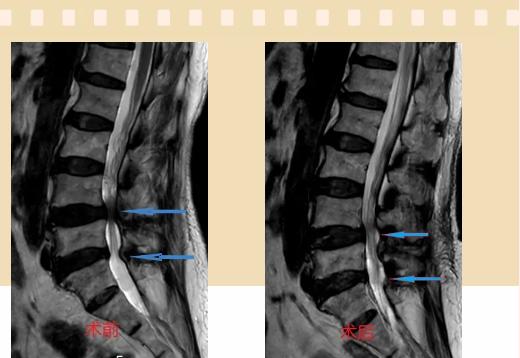

入院后李鵬副主任醫(yī)師為其進行了詳細的查體,完善了術前的檢查,明確診斷為:腰椎管狹窄癥(L4/5、L5/S1),病人合并2型糖尿病,請內分泌科會診,穩(wěn)定血糖后,麻醉科會診病人,排除手術禁忌,李鵬為病人制定了手術方案:單側入路雙側減壓(ULBD)。

手術采用三個微創(chuàng)小切口,兩個節(jié)段減壓手術時間2.5小時,出血50ml。術后2天腰圍保護下床活動,術后5天順利出院。

傳統(tǒng)腰椎管狹窄癥的手術治療,往往需要切開減壓,同時需要內固定融合術,創(chuàng)傷很大,同時可能需要輸血,臥床時間較長,病人合并糖尿病,感染風險也高,而本次采用的UBE-ULBD手術切口更小(加起來約3cm,如果是單節(jié)段狹窄只需要不到2cm切口)、創(chuàng)傷更小,術后恢復較快,可以更早地恢復正?;顒印?/div>

此外,手術保留了病變節(jié)段的穩(wěn)定性,是一種微創(chuàng)的椎管減壓手術,能通過切除部分椎板、關節(jié)突關節(jié)、黃韌帶來解除神經根和硬膜囊的壓迫,不需要額外行腰椎內固定術,不需要螺釘及融合器的植入,病人術后腰椎的活動度不受影響。(盧 闖 劉 旭 袁錦鈺)